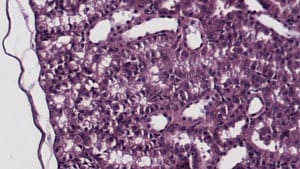

Conservative Smoothing Filter — Before

Conservative Smoothing Filter — After